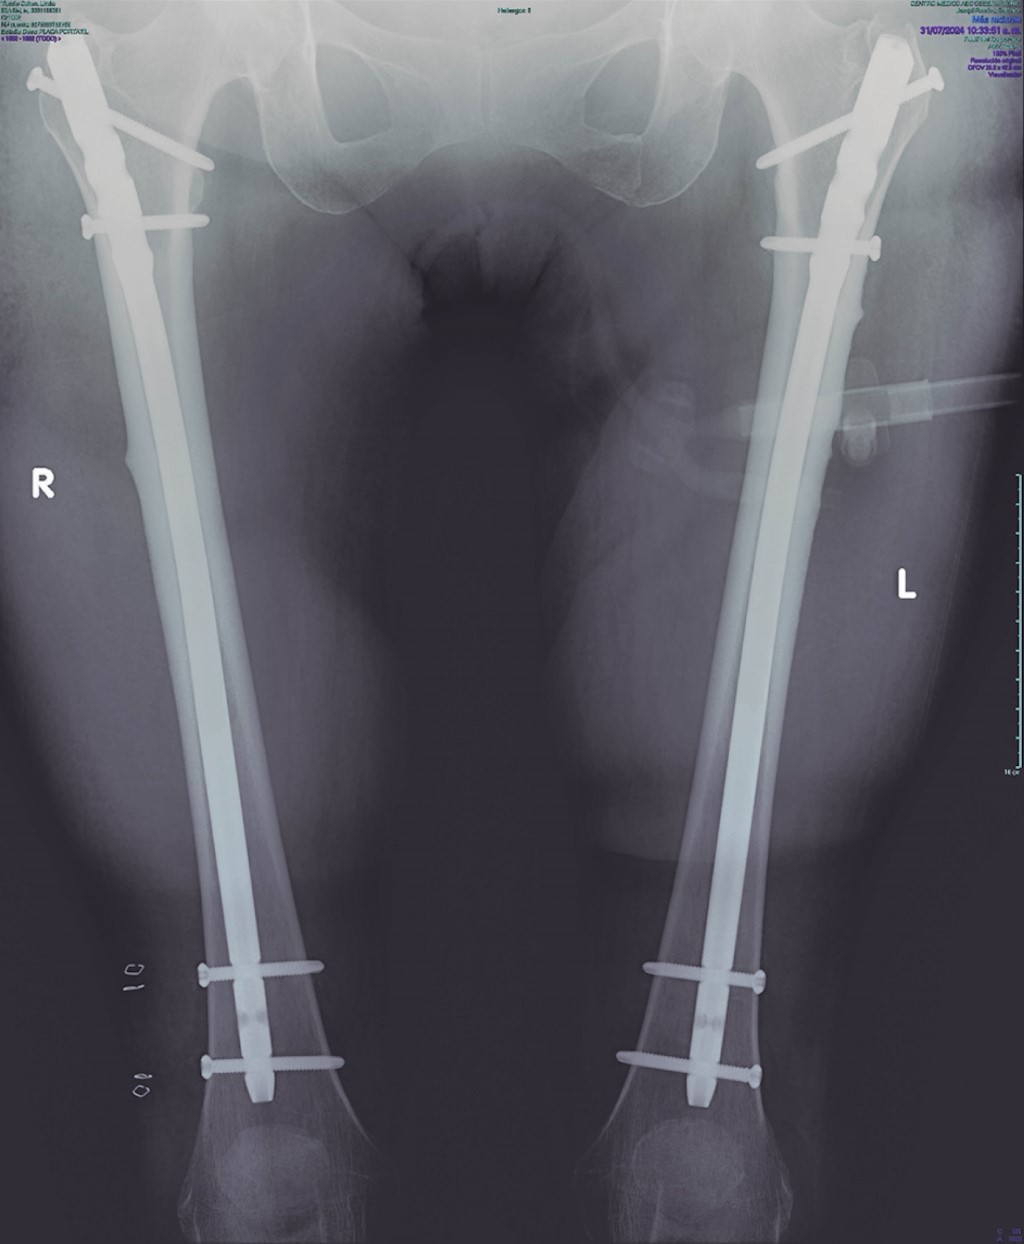

A 76-year-old female patient used alendronate for four consecutive years, switching afterward to zoledronic acid and using it for five more years, making it a total of nine years of BISPH use. She arrived at the emergency room after experiencing a spontaneous fracture of the left femur while taking a walk (Figure 3), leading to a fall from her height. The clinical examination and radiographs demonstrated a left Atypical Femur Fracture (AFF). Upon further observation, an incomplete fracture was found in the right femur (Figure 4). She underwent a first surgical intervention, and two days later, a second one; intramedullary nailing was performed in both femurs (Figure 5). A lumbar spine dual-energy X-ray absorptiometry (DEXA) was performed, which reported a T Score of −0.9, spine TBS of 1.382, left femoral neck T-score of −1.5, and right femoral neck T-score of −1.7, leading to an osteopenia diagnosis.

Figure 3

Figure 4